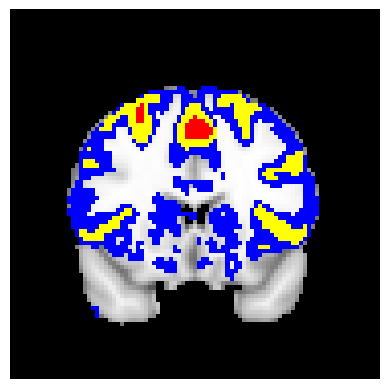

The confidence regions are constructed on fMRI scans from 77 subjects as a real data application of the proposed methods after applying additional smoothing with Gaussian kernel with FWHM to match the results shown in Bowring (2019) [BOWRING2019116187]. Confidence regions using 1) the joint method with , 2) the separate method with BH adjustment for upper and lower side each with , 3) the separate method with BH adjustment for upper side and two-stage adaptive procedure for lower with , and 4) SSS () were compared with threshold level 1.0%, 1.5%, and 2.0% Blood Oxygenation Level Dependent (BOLD) change. Joint control confidence regions are produced with instead of 0.05 for the reasons mentioned in chapter 3.

For all slices, FDR controlling methods show tighter inference of both upper and lower CR compared to the SSS method. SSS shows smaller upper CR and larger lower CR which suggests more conservative inference compared to FDR controlling testing based methodologies. This is due to the fact that by controlling for FDR, the method allows for more false discoveries in exchange for more discoveries in general. Despite having higher level at , joint control confidence regions still show comparable results to other methods even with higher significance level. Naturally, as the threshold goes up, the area enclosed between the upper and lower confidence regions decreases.

Confidence regions with separate controls of FDR for lower and upper are presented in two forms for comparison: one with BH procedure for the lower confidence region, and the other one with the two-stage adaptive procedure for the lower confidence region. The upper confidence region remains the same as both methods uses BH procedure for the upper set FDR control. Lower confidence regions with adaptive method are smaller than lower sets with BH procedure which is to be expected as the two-stage adaptive procedure is less conservative when more voxels are thought to be rejected. In the context of negative one-sided testing, this is equivalent to when there are less number of voxels above than below .